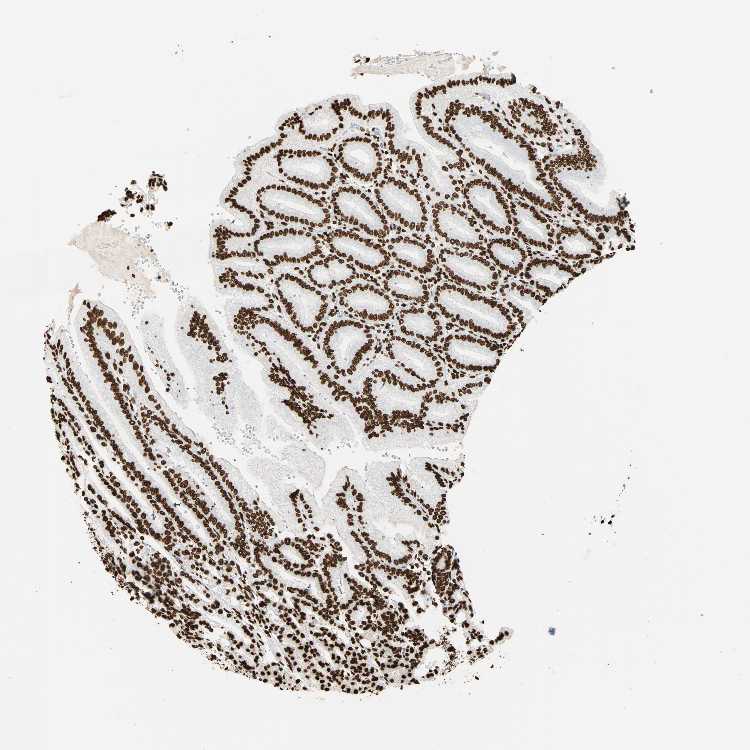

STOMACH 1 - Antibody stainingi

Antibody staining in the annotated cell types in the current human tissue is reported as not detected, low, medium, or high, based on conventional immunohistochemistry profiling in selected tissues. This score is based on the combination of the staining intensity and fraction of stained cells.

Each image is clickable and will lead to virtual microscopy that enables deeper exploration of all samples and also displays staining intensity scores, fraction scores and subcellular localization as well as patient and tissue information for each sample.

Antibody CAB008558

Glandular cells High